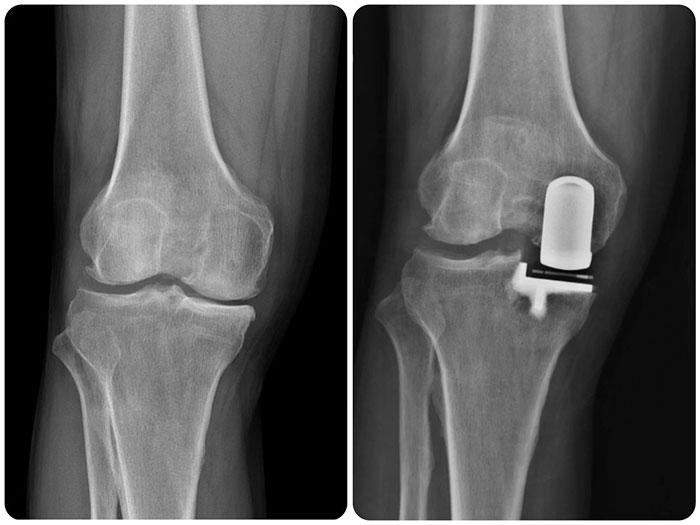

手術中,白玉明主任親自主刀,行膝關節(jié)內側縱向約10cm切口,充分顯露膝關節(jié),探查可見內側間室股骨髁及脛骨平臺軟骨明顯磨損,大部分軟骨下骨裸露,呈骨對骨狀態(tài),髕股關節(jié)及外側間室軟骨Ⅰ~Ⅱ度磨損,前交叉韌帶完整;應用磨具對內側股骨髁及脛骨平臺進行成型,試行屈伸間隙平衡,并進行單髁膝關節(jié)假體安裝。術后第2天患者即可自主下地活動,臨床疼痛癥狀完全消失,膝關節(jié)屈伸活動無受限,患者及家屬對治療效果非常滿意。

其中膝關節(jié)單髁置換術(UKA)是指僅對膝關節(jié)病變的內側或外側室軟骨進行表面置換,不干擾膝關節(jié)其他正?;蚪跽5牟糠?,從而以最小的創(chuàng)傷獲得最大的收益。膝關節(jié)單髁置換術手術創(chuàng)傷小,術后恢復快、并發(fā)癥少、術后功能好,還保留了膝關節(jié)前后叉韌帶及本體感覺,術后病人的感覺好,活動更自如。